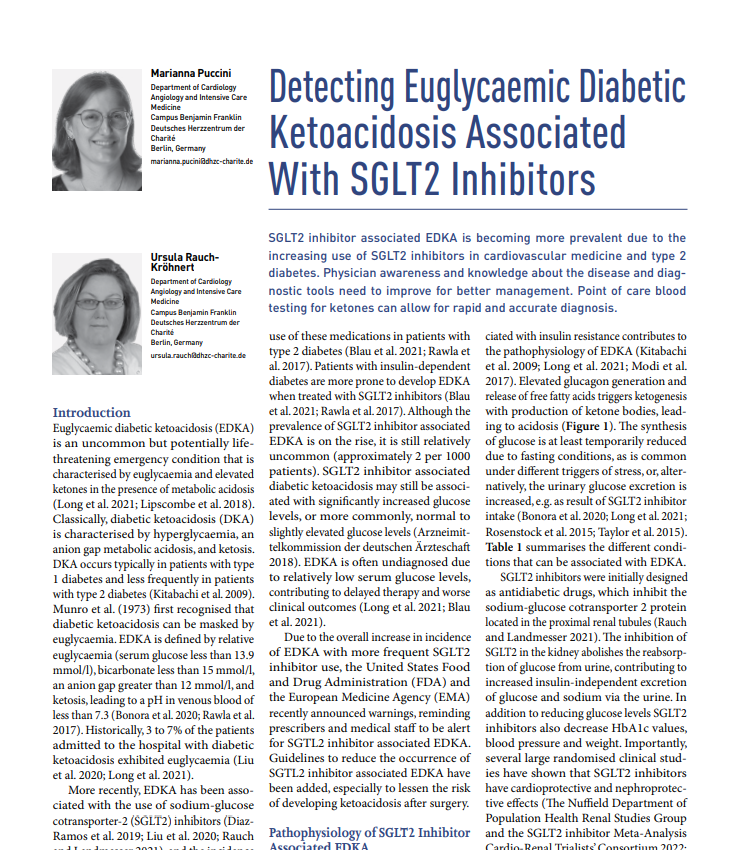

The diagnosis of #EDKA should be suspected in patients on #SGLT2 inhibitors and #ketones should be measured promptly to avoid progression to life-threatening disease. Read more iii.hm/novabioicu22023 Nova Biomedical Marianna Puccini #euglycaemic #diabetic #ketoacidosis